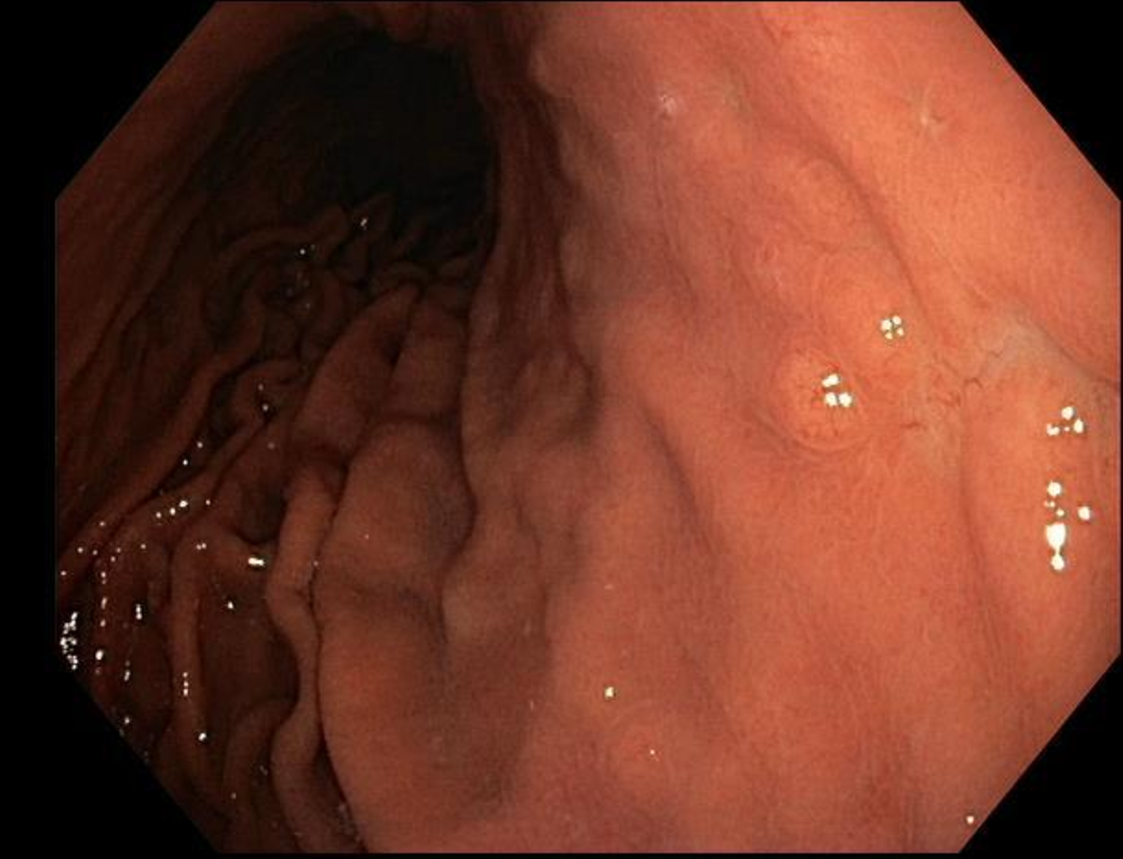

Imaging and Staging for Stomach Malignancy

- Endoscopic ultrasonography (EUS) is a currently the mainstay in diagnosis and staging of gastric tumors.

- EUS FNA offers precise diagnosis for primary tumors, local invasion, and lymph node sampling.